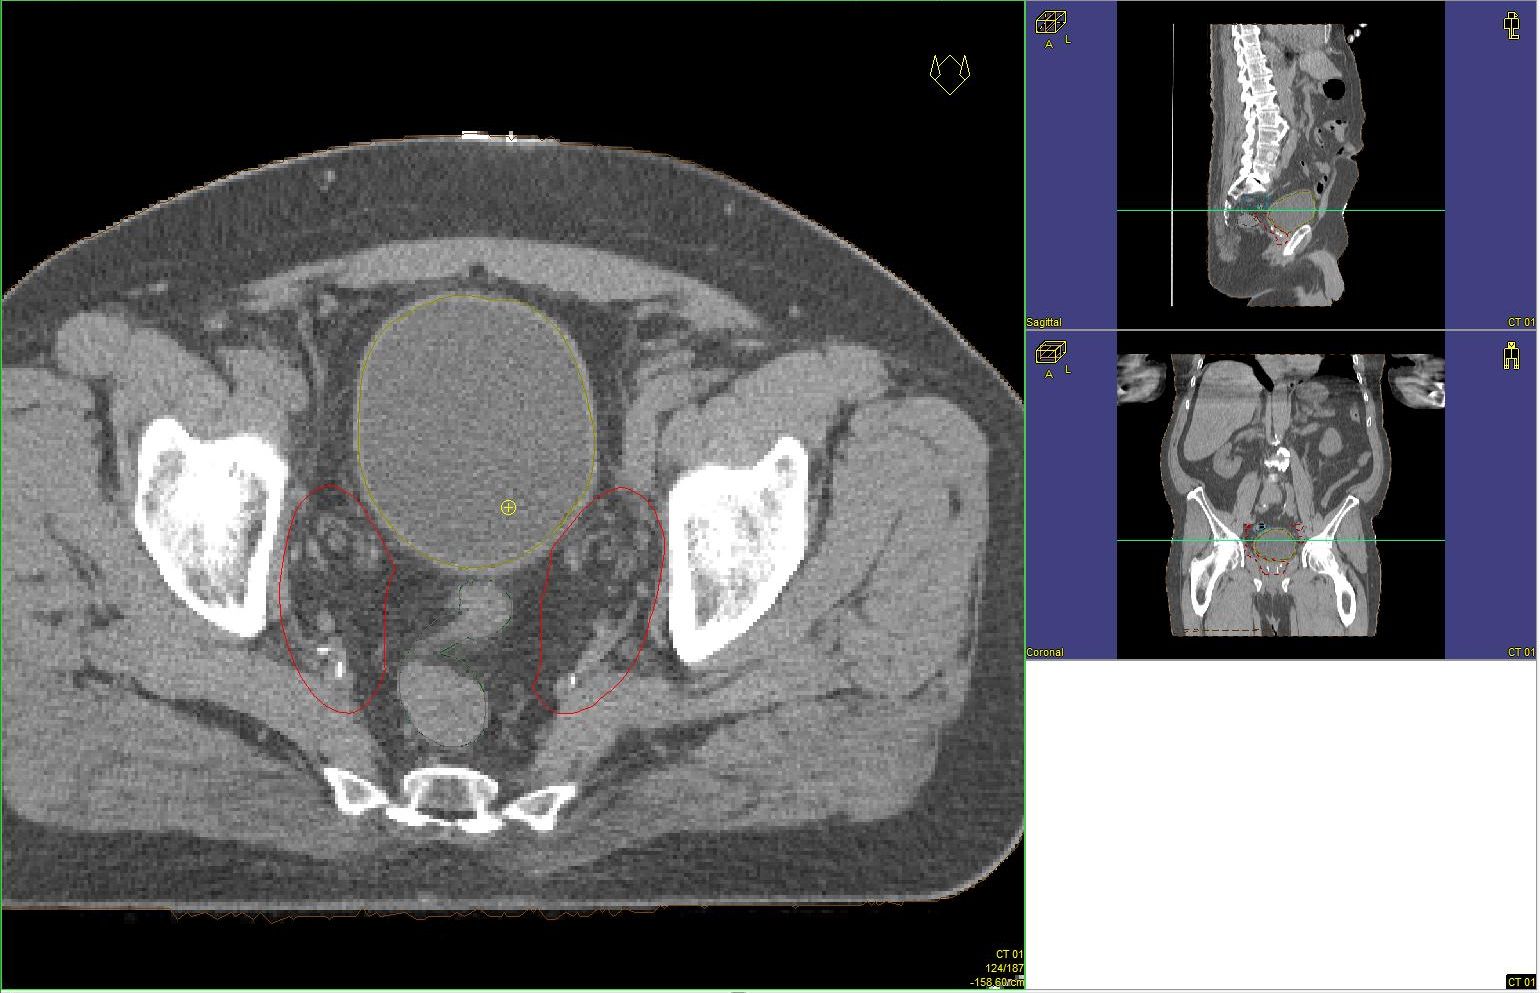

Prostata-Ca: Zielvolumen der postoperativen Radiotherapie

Beispiel: postoperative RT